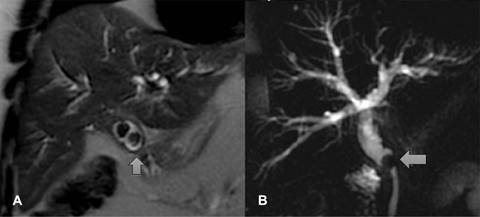

La principal causa de obstrucción intraluminal benigna fue la coledocolitiasis asociada o no a colecistectomía (Figura 1). Las causas extraluminales son las menos frecuentes y son ocasionadas principalmente por patologías malignas condicionantes de efecto de masa en la vía biliar; las principales causas reportadas fueron la neoplasia pancreática (Figura 2), seguida de la neoplasia gástrica y conglomerados ganglionares. Dentro de las causas benignas de obstrucción extraluminal se encontraron: hipertonía del esfínter de Oddi y pancreatitis.

Figura 1: Masculino de 57 años con antecedente de dolor abdominal e ictericia. (A) Presencia de dos litos en la vesícula. (B) Se observa lito (flecha) en colédoco que ocasiona obstrucción y dilatación de la vía biliar intrahepática y extrahepática.